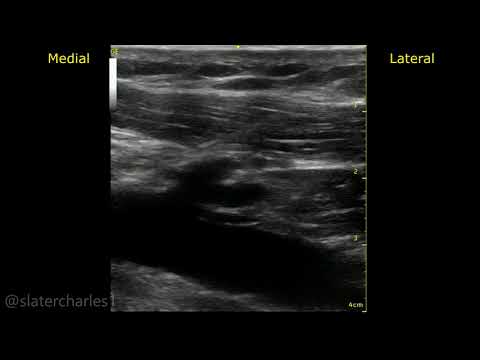

Another case LV lead pulled back now target is occluded. Sleeve tied tight directly to the muscle but then turned to scar. Can't tie directly to the muscle with enough tension to pass tug test without causing necrosis then scar. Tie to the Knot. #EPeeps @narrowQRS @rdschaller